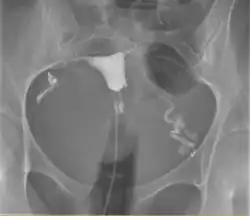

A normal hysterosalpingogram. Note the catheter entering at the bottom of the screen, and the contrast medium filling the uterine cavity (small triangle in the center).

Hysterosalpingography (HSG), also known as uterosalpingography,[1] is a radiologic procedure to investigate the shape of the uterine cavity and the shape and patency of the fallopian tubes. It is a special x-ray procedure using dye to look at the womb (uterus) and fallopian tubes.[2] In this procedure, a radio-opaque material is injected into the cervical canal, and radiographs are taken. A normal result shows the filling of the uterine cavity and the bilateral filling of the fallopian tube with the injection material. To demonstrate tubal patency, spillage of the material into the peritoneal cavity needs to be observed. Hysterosalpingography has vital role in treatment of infertility, especially in the case of fallopian tube blockage.